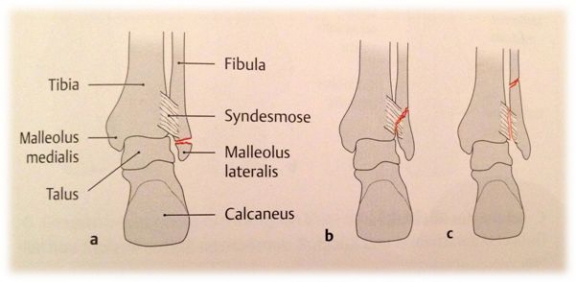

An ankle joint fracture is most often divided into three different forms by Weber's classification based on the height of the fracture at the fibula (outer ankle):

Weber A: Outer ankle fracture below syndesmosis (→ Syndesmosis always intact)

Weber B: Outer ankle fracture at syndesmosis level (→ Syndesmosis possibly injured)

Weber C: Outer ankle fracture above syndesmosis (→ Syndesmosis always injured)

Fig. 2) Weber classification for ankle fractures (from: Prometheus ®, MLP)

In all three Weber forms, the inner ankle can also be broken or the inner ligament injured. However, this is not a criterion for this classification.